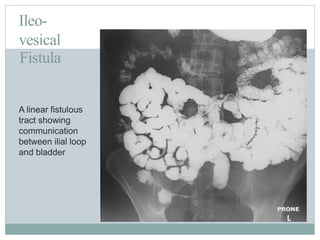

Ileo-

vesical

Fistula

A linear fistulous

tract showing

communication

between ilial loop

and bladder